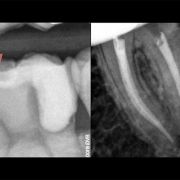

Restoring root canal treated tooth... A Conservative approach!

Based on evidence, all posterior teeth should be restored with cuspal coverage after root canal treatment. However, most of these teeth are badly destructed due to caries or large existent restoration. The key of success is to preserve the remaining tooth structure and restore the tooth conservatively. Dr khalid Merdad and I worked simultaneously to accomplish this task.